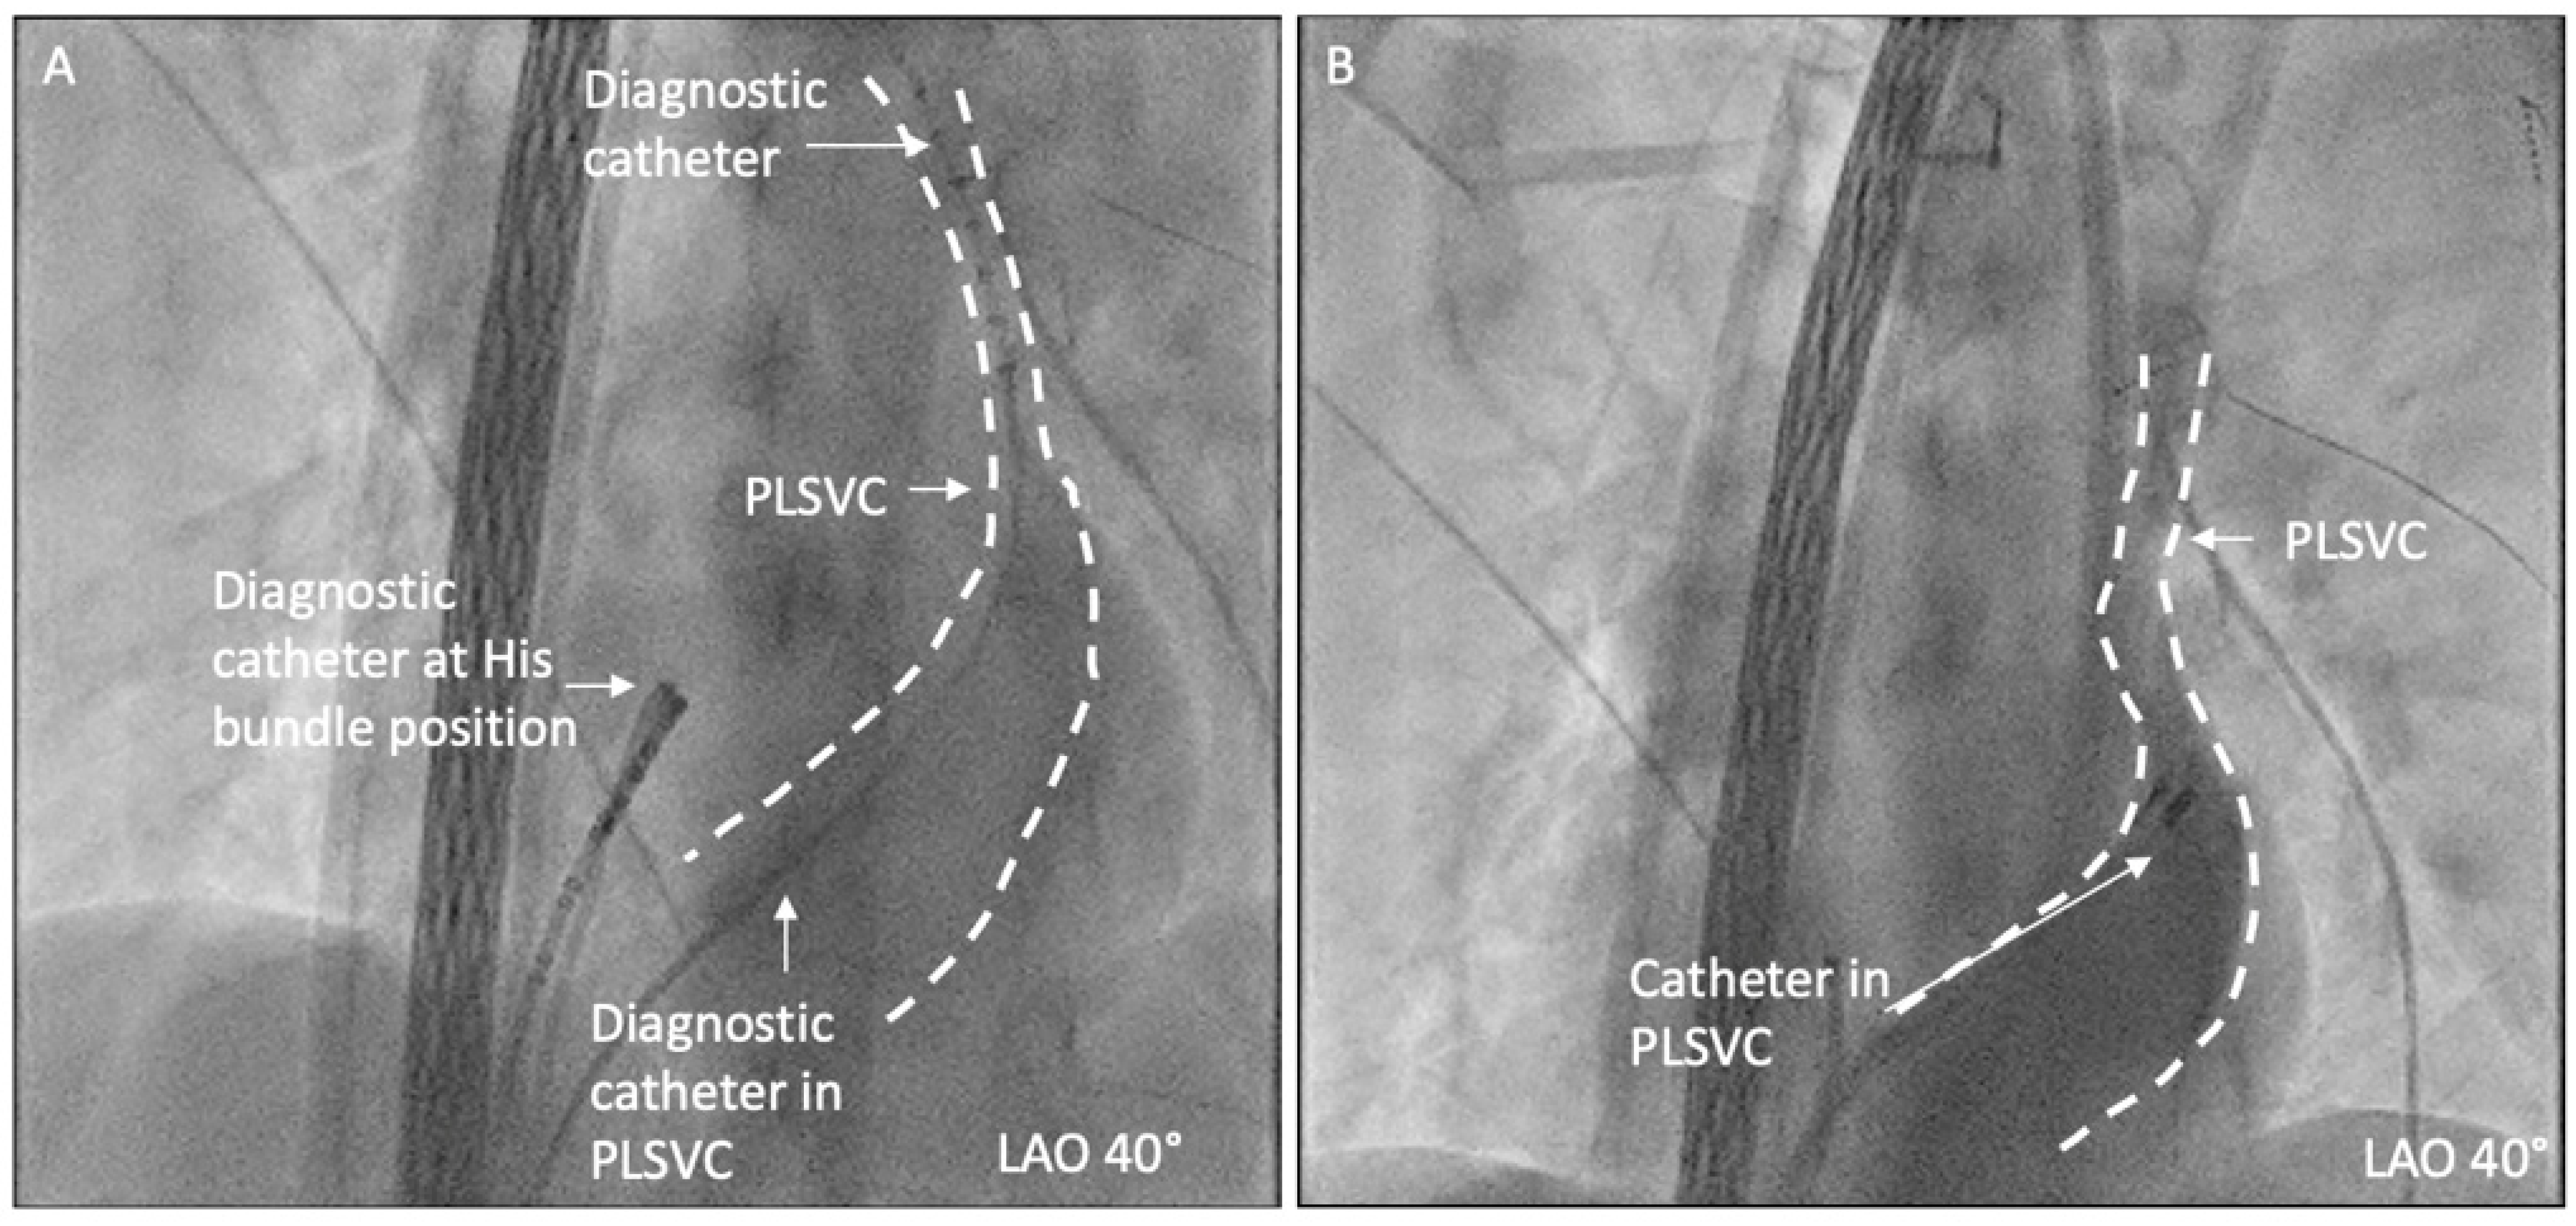

2.2. Diagnostic Workup

2.3. Ablation Strategy